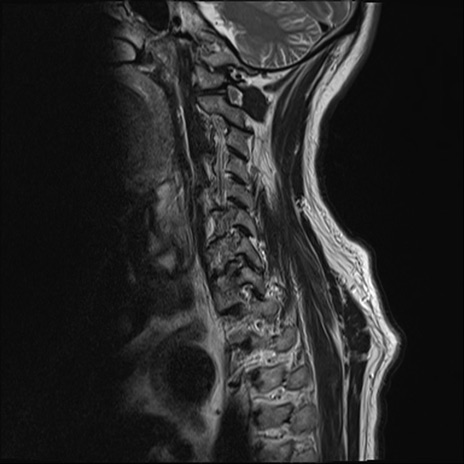

【整形】TIPS症例7 頚椎MRI T2WI(矢状断像)

頚椎MRI

T1WI(矢状断像)